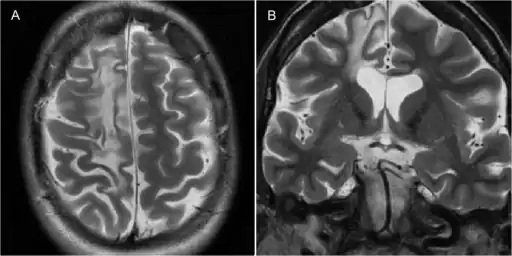

The diagnosis may be made based on the symptoms alone, after ruling out other possible causes. An EEG will usually show the electrical features of epilepsy and slowing of brain activity in the affected hemisphere, and MRI brain scans will show gradual shrinkage of the affected hemisphere with signs of inflammation or scarring.[14]

-

Rasmussen encephalitis resulting in atrophy of the right frontal lobe as seen on MRI.[16]